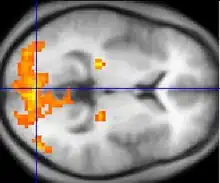

L'appareil IRM est parfois désigné sous le nom de « scanner », ce qui en français prête à confusion avec le tomodensitomètre. Contrairement à ce dernier (et à d'autres techniques d'imagerie comme la TEP), l'examen IRM n'est pas invasif et n'irradie pas le sujet. Cela en fait donc un outil de prédilection pour la recherche impliquant la personne humaine, et notamment en neurosciences cognitives. À partir des années 1990, la technique d'IRM fonctionnelle, qui permet de mesurer l'activité des différentes zones du cerveau, a en effet conduit à des progrès importants dans l'étude des fondements neurobiologiques de la pensée.

La principale innovation dans le domaine de l'IRM viendra avec la reprise par Seiji Ogawa des travaux de Linus Pauling et Charles Coryell sur le magnétisme de l'hémoglobine. En effet, le signal IRM émis par le sang oxygéné diffère du signal du sang désoxygéné. Cette propriété permit donc à Ogawa, John Belliveau et Pierre Bandettini de réaliser en 1992 les premières images du cerveau en fonctionnement : en réponse à des stimulations visuelles, ils purent mesurer une augmentation du débit sanguin cérébral dans les aires visuelles du lobe occipital. La mesure de cette réponse hémodynamique est à la base du fonctionnement de l'imagerie par résonance magnétique fonctionnelle, un outil central des neurosciences cognitives contemporaines.

IRM fonctionnelle (IRMf)

En suivant la perturbation du signal de RMN émis par cette molécule, il est donc possible d'observer l'afflux de sang oxygéné, qui chasse le sang désoxygéné. Lorsqu'une zone du cerveau augmente son activité, un afflux de sang oxygéné lui parvient grâce à un mécanisme combinant la dilatation des vaisseaux sanguins à divers autres mécanismes mal élucidés, ce qui répond ainsi à la demande de consommation locale en dioxygène des cellules actives : c'est le signal BOLD. En faisant l'acquisition d'images pondérées T2* à une cadence rapide (environ une image toutes les secondes, voire moins), il est possible de suivre en direct, sous forme de film, les modulations de débit sanguin liées à l'activité cérébrale, par exemple lors d'une tâche cognitive.